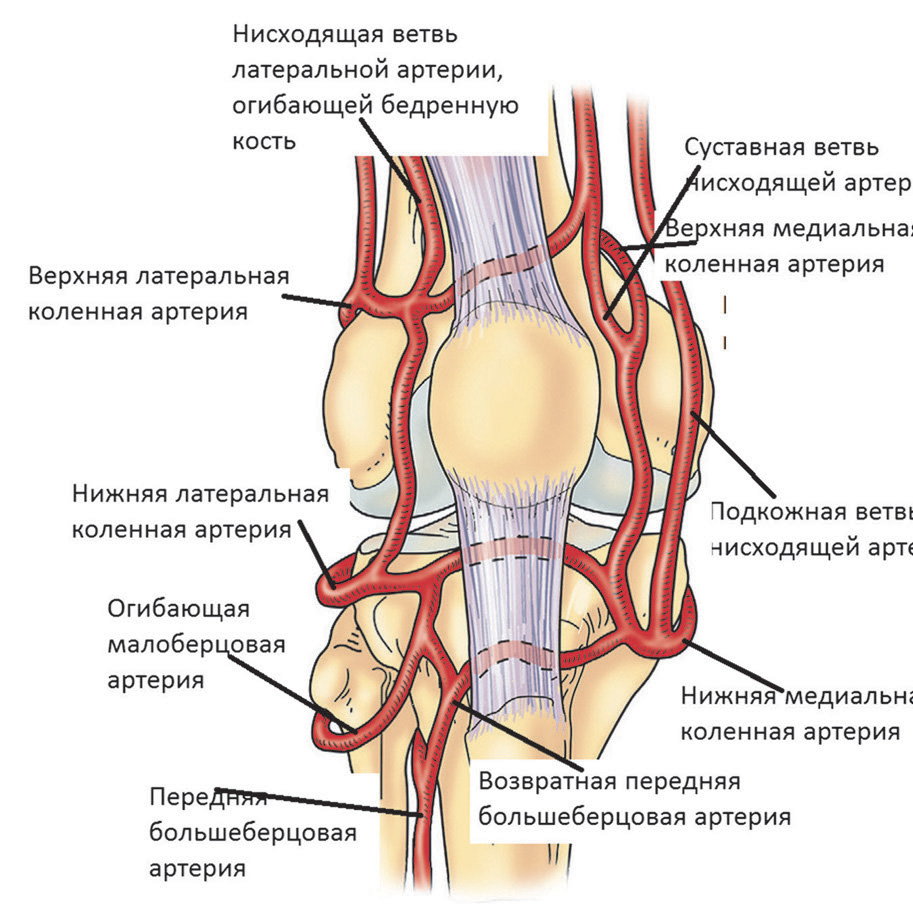

Причины и лечение травм коленного сустава